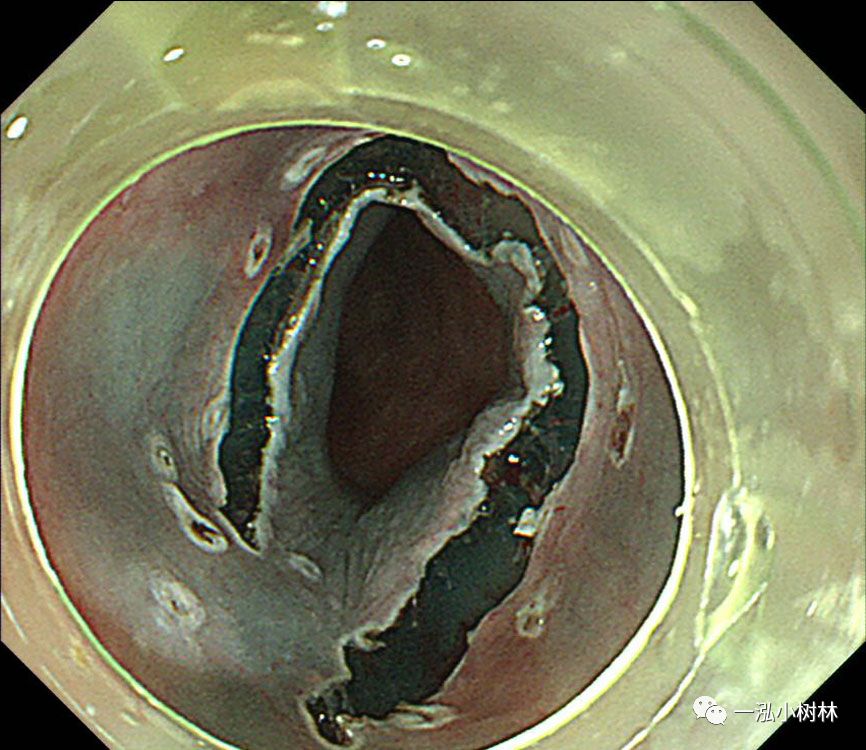

图5 在近端(口侧)进行黏膜切口